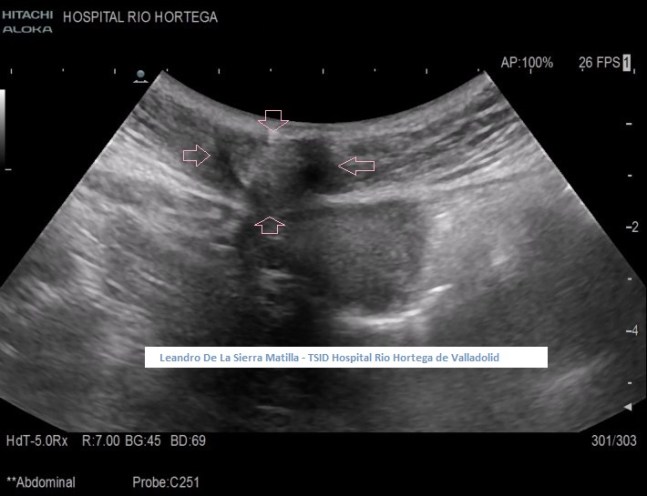

Se realiza estudio de Ecografía Abdominal protocolizado, en el que se observan entre otros hallazgos, varias lesiones esplénicas y ováricas (flechas rosas) junto con una mínima cantidad de líquido libre abdominal.(FIG 1,2 y 3)

1

2

3